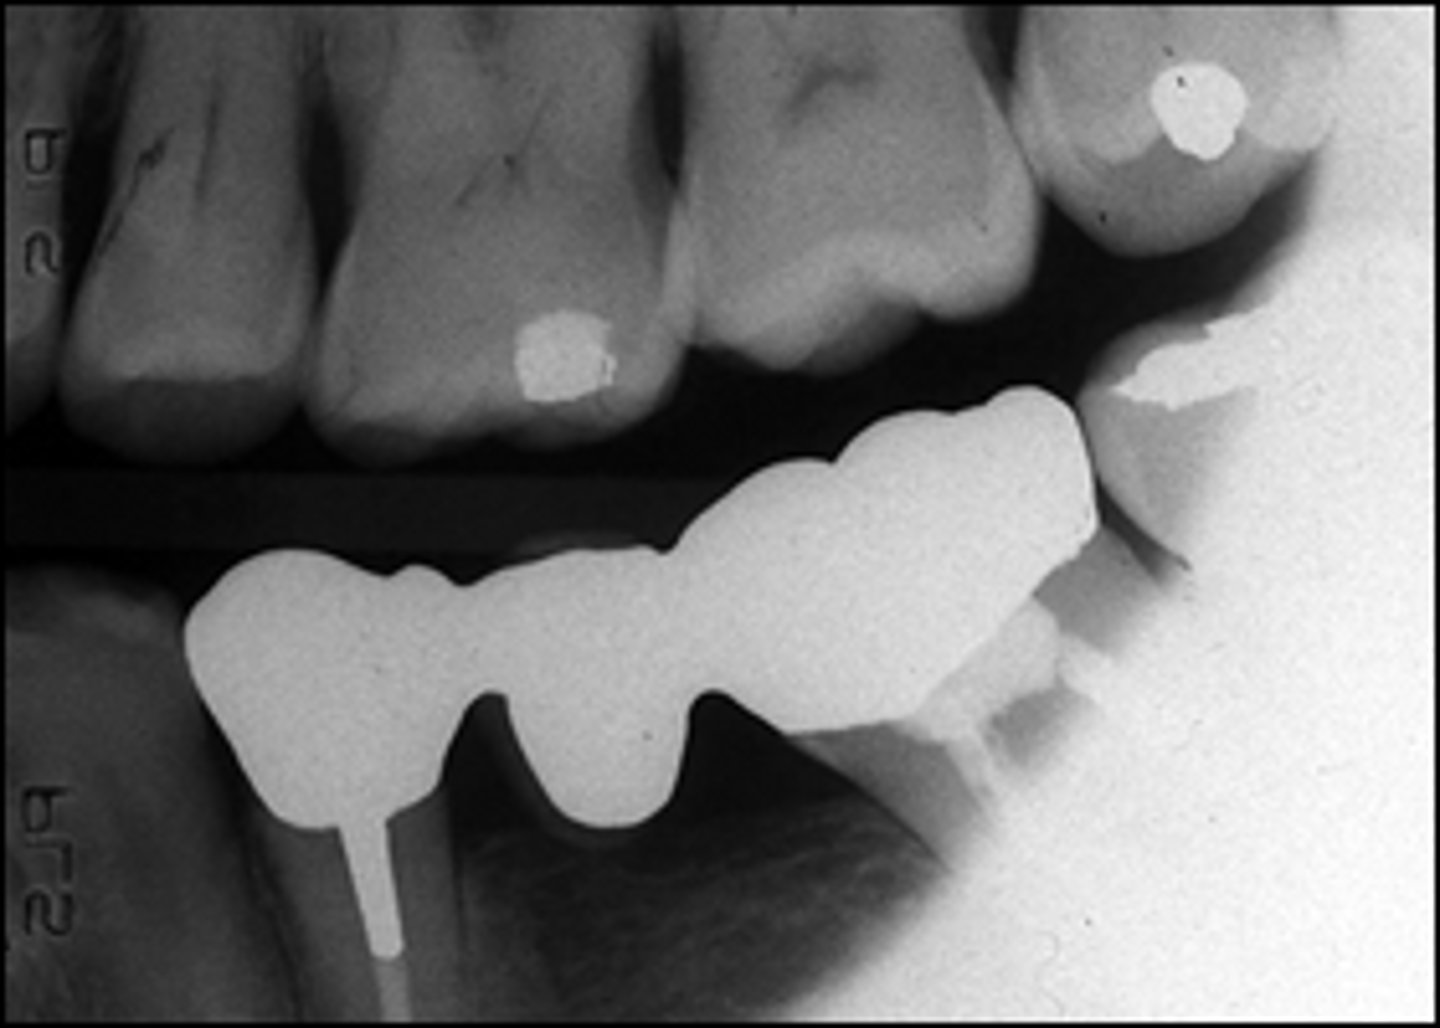

What is wrong with this image?

The image is cone cut